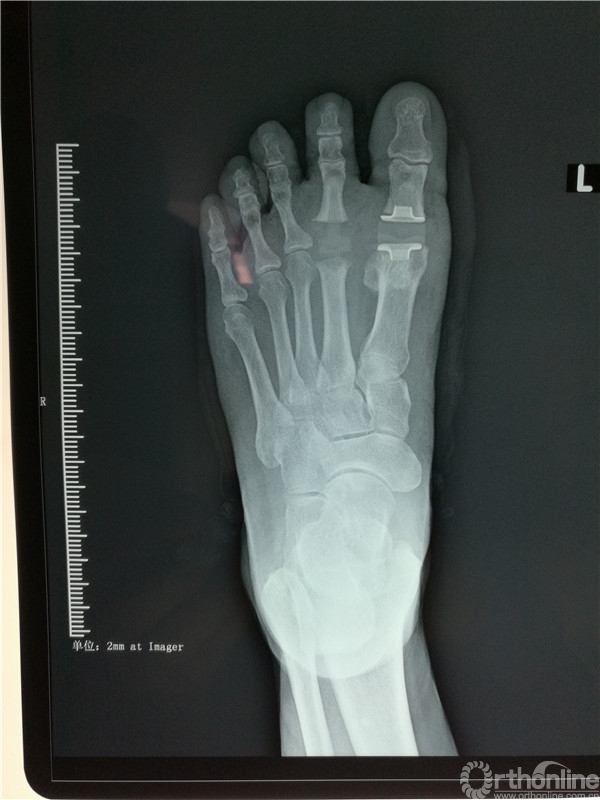

2016年4月7日,烟台市烟台山医院南院骨科收治一例左足跖趾关节骨性关节炎的病人,患者左足严重疼痛10余年,要求治疗的心情迫切。

在张树栋院长及刘克贵主任的支持下,南院骨科组织多次病例讨论,制定了一套对病人有效的治疗方案。以刘克贵主任,孙冰,李宏彦组成的医疗小组。于2016年4月9日上午九时,在腰麻下行左足第1、2 跖趾关节人工关节置换术,患者术后左足的疼痛明显减轻,功能良好,外形美观。